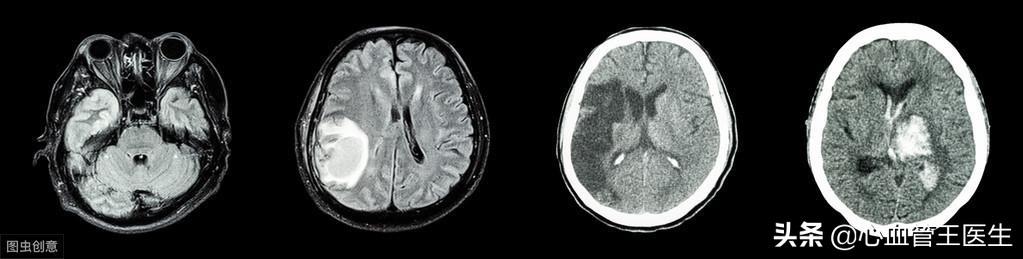

L'hémorragie cérébrale est définie comme un saignement causé par la rupture non traumatique de vaisseaux sanguins dans le parenchyme cérébral. Elle représente 20 à 30 % de tous les accidents vasculaires cérébraux, avec un taux de mortalité aiguë de 30 à 40 %, principalement en raison d'une hypertension artérielle non détectée ou d'un contrôle inefficace de l'hypertension artérielle.

L'hémorragie cérébrale hypertensive est légèrement plus fréquente chez les hommes, elle a tendance à se produire en hiver et au printemps, elle survient généralement pendant les activités et l'excitation émotionnelle, il n'y a pas de signes prémonitoires avant l'hémorragie, la moitié des patients ont un mal de tête très sévère et les vomissements sont fréquents, la pression artérielle augmente considérablement après l'hémorragie, les symptômes cliniques atteignent souvent leur maximum en quelques minutes à quelques heures, les signes cliniques et les symptômes varient en fonction de la localisation de l'hémorragie et de l'importance de l'hémorragie, les noyaux basaux, le thalamus et l'hémorragie de la capsule interne provoquant une hémiparésie légère est un symptôme précoce courant ; des crises d'épilepsie se produisent dans quelques cas, souvent focales ; les cas graves tombent rapidement dans l'inconscience ou dans le coma. L'hémorragie des noyaux basaux, du thalamus et de la capsule interne provoquant une hémiparésie légère est un symptôme précoce courant ; une crise d'épilepsie survient dans quelques cas, souvent focale ; dans les cas graves, le patient passe rapidement à une conscience floue ou au coma.

En effet, l'hémorragie cérébrale et l'infarctus cérébral se comportent souvent de la même manière, et il nous est difficile de les distinguer à partir des symptômes, qui doivent être précisés après un scanner à l'hôpital.

3) Hémorragie cérébrale : la pression dans les vaisseaux sanguins est relativement élevée dans cette capacité tampon de régulation des troubles, la rupture des vaisseaux sanguins, grave, peut être un coma momentané, des vomissements, l'étendue de cette hémorragie cérébrale dans le tronc cérébral après l'endommagement des vaisseaux sanguins importants, le centre respiratoire de l'inhibition des signes vitaux ainsi que l'incidence du choc cardiogénique.

L'infarctus cérébral est dû à l'hypertension artérielle qui entraîne l'athérosclérose des artères cérébrales et la formation de plaques, ce qui bloque les vaisseaux sanguins cérébraux et provoque un infarctus dans le cerveau ; l'hémorragie cérébrale est due à l'élévation prolongée de la pression artérielle, qui entraîne une fragilisation des artères cérébrales, une réduction de leur élasticité ou la formation de micro-anévrismes, ce qui provoque une rupture vasculaire en raison d'une pression supérieure à la capacité des vaisseaux cérébraux. Rupture des vaisseaux sanguins. Après la rupture des vaisseaux sanguins cérébraux, une grande quantité de sang s'engouffre dans la cavité crânienne et comprime les tissus cérébraux, ce qui peut entraîner des maux de tête, des vomissements, des troubles de la conscience et d'autres symptômes. L'hémorragie cérébrale est une complication présentant un facteur de risque élevé, et le taux de mortalité atteint 35 à 52 % dans les 30 jours suivant la survenue de l'hémorragie cérébrale ; en même temps, il s'agit également d'une complication présentant un degré de gravité plus élevé, et environ 80 % des patients ne peuvent pas retrouver la capacité de s'occuper de leur propre vie après 6 mois. Par conséquent, l'hémorragie cérébrale est une complication qui doit être évitée par les patients hypertendus, et l'abaissement de la tension artérielle est la principale mesure pour réduire le risque d'hémorragie cérébrale.